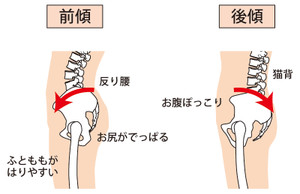

骨盤傾斜性腰痛症(深腰、反り腰)

この症状は

骨盤傾斜が長期間、本来の角度と異なった状態が継続すると発症します。

一般的に人の骨盤傾斜角度は男性で50度から60度の間で、女性で55度から65度の間で角度を作っています。

骨盤傾斜が深くなり過ぎたり(深腰)、

又反対に骨盤傾斜が浅くなり過ぎたり(反り腰)すると腰痛が発生します。

例えば、

深くなると椅子に座っていたり、台所で家事などがつらくなります。(深腰)

逆に

浅くなると反り腰になり、仰向けで寝たり、前かがみの姿勢で痛みが出ます。(反り腰)

このような骨盤角度の変位はすべて筋肉のなせることです。

状態は

骨盤角度が深いと椎体(背骨)は常にストレートぎみになっており(深腰)、

骨盤角度が浅いと椎体(背骨)はより強く前湾します(反り腰)。